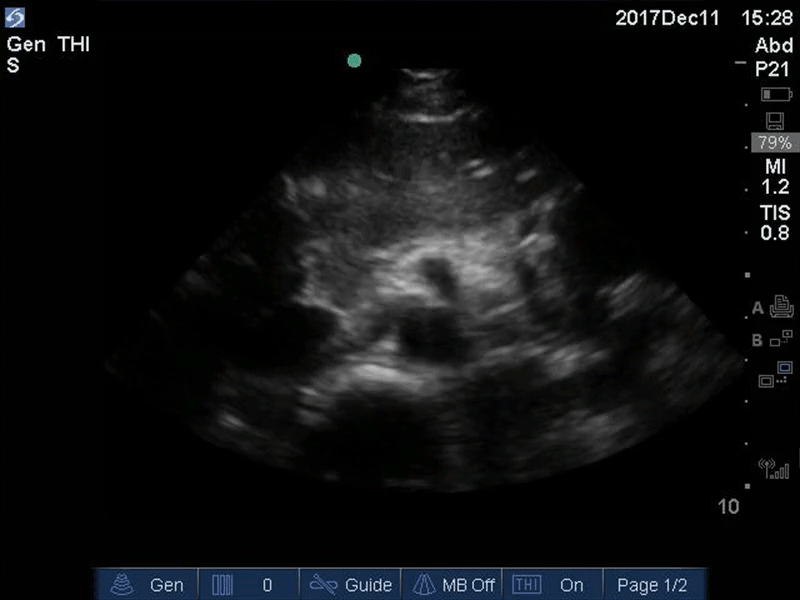

Good Seagull Sign Orange: Spine, Red: Aorta, Blue: IVC, Green: Portal venous confluence, Pink: “Seagull sign” aka celiac trunk Images: Dr. Lindsay Davis, Dr. Hannah Kopinski. Image Editing: Michael Amador and Dr. Matthew Riscinti